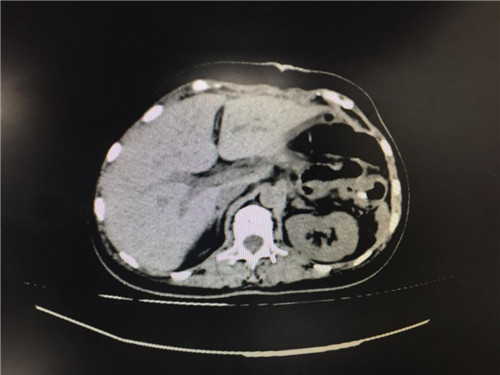

2月12日,普外科收治了一名女性患者,该患者入院一个月前,无明显诱因出现上腹部疼痛不适,呈间断性,向腰背部放射,有恶心,无呕吐,近一个月体重下降了5kg。门诊查上腹部CT提示:胰颈部新生物并胰管扩张;副脾。

患者病情复杂,在潘承恩教授和全科医生的讨论下,结合检验及检查结果,术前胰腺颈体部肿瘤诊断明确,科室积极制定手术方案,详细向家属探明病情并取得合作。2月21日,由普外科史和平主任、梁鹏锋医师主刀,在王谦、李垚磊医师配合下,成功对该患者实施了剖腹探查、全胰腺切除、脾脏切除术。手术中发现,患者胰腺颈体部可触及一大小约4cm包块,胰头部质软,胰腺体尾部质硬,遂决定行胰腺颈体尾部切除及脾脏切除术。在胰腺近侧断端切取部分胰腺组织送术中快速冰冻,提示查见异型增生的胰腺腺泡样组织,联系病理科考虑癌细胞残留,术中向家属谈明病情并取得同意,遂行胰十二指肠切除术,手术顺利,术后生命体征平稳,并于术后第四日进行了复查CT结果良好。